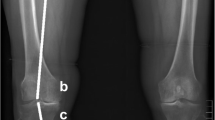

Three-dimensional proximal tibial sclerotic bone models

From January 2018 to January 2019, patients with knee OA and severe genu varum over 15° were selected for 0.6 mm thin-layer CT scanning of both lower extremities and 3-D modelling using Mimics 14.0 (Materialize, Leuven, Belgium) A severe varus OA case’s clinical images were shown in Fig. 1. Patients with rheumatoid arthritis, suspected preoperative infection, or who previously underwent knee surgery were excluded from the study. The following coordinate system was established for the modelling, as shown in Fig. 2: the z-axis was the tibial MA, which was defined as the line connecting the center of the ankle joint and the center of the random axial levels below the articular surface of the proximal tibia and above the tibial tuberosity; the y-axis was defined as the anterior-posterior (AP) axis, which was the connection between the medial edge of the tibial tuberosity and the midpoint of the posterior cruciate ligament after an experienced orthopedist recommended omitting the effect of the osteophyte in the plane perpendicular to the z-axis; the line perpendicular to the y-z axis was defined as the x-axis, and the fibula was disregarded to simplify the model (Fig. 2e). The tibial cut was performed on the plane perpendicular to the tibial MA and 8 mm below the lateral tibial plateau surface. Cases were included in the study if there were no defects in the medial tibia. If there was a defect in the medial tibia less than 4 mm from the tibial cut plane, the amount of lateral tibial cut was increased until the defect was removed, and the case was included. If the medial defect was greater than 4 mm, the case was excluded. Among those 120 cases, 4 cases were excluded from the study based on a preoperative posterior drawer test which was strongly positive (+++) and subsequent diagnosis of posterior cruciate ligament injury. According to these criteria, a total of 116 patients were included in the study. Basic statistical data are shown in Table 1.